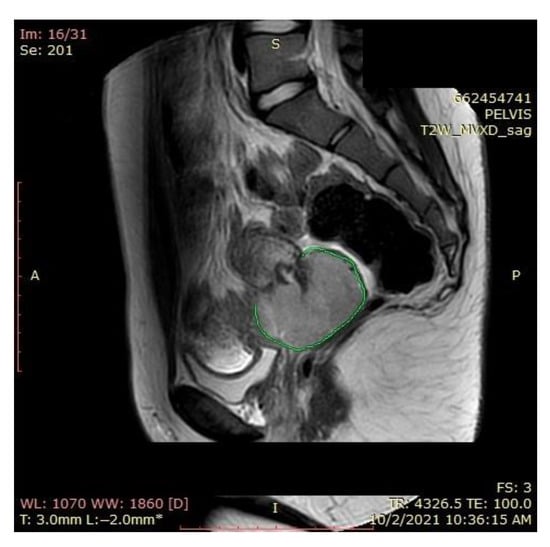

A pelvic MRI was recommended to our patient, as it would be able to provide an accurate anatomic localization of the mass and its relationship with the surrounding organs. It revealed an expansive solid cervical mass that developed between the internal and external cervical orifice, occupying the left vaginal recess, with imprecise boundaries being observed at this level. Axial and sagittal T2-weighted images showed a 53 × 78 × 46 mm mass that was hyperintense compared to normal myometrium, and axial T1-weighted images showed an isointense mass compared to the myometrium that was occupying the uterine cervix and upper vagina. The ovaries and the uterine body were normal in size, and a right external iliac adenopathy was also detected (Figure 1).

An MRI scan performed immediately the next day after finishing the radiotherapy and chemotherapy sessions showed a significant favorable response, with the persistence of a necrotic and ulcerative cervical area and a possible residual lesion on the right side of the cervix (Figure 12).

Figure 1. Pelvic sagittal T2–weighted sequence: the green highlighted area represents the circumferentially developed cervical tumor mass with intermediate T2 signal that includes both the endo- and the ectocervix protruding into the upper vagina.

Figure 12. Favorable postradiotherapy response with the reduction in cervical mass (the green highlighted area represents the cervical tumoral mass).